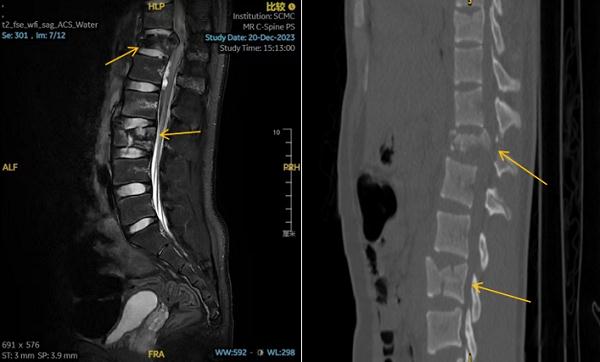

术前CT示胸腰椎多发爆裂性骨折伴移位

15岁的孟迪(化名)在夜间“梦游”时,不慎从6楼家中坠落,一小时后才被人发现。当时他虽意识清醒,但双下肢已无法站立,感觉麻痹。家属立即拨打120将孩子送至上海交通大学医学院附属上海儿童医学中心急诊。入院后, CT结果提示其胸、腰椎多发爆裂骨折,情况十分危急。

儿中心骨科王志刚主任团队接诊后,对孟迪的病情进行了详细的分析,为其制定了个性化的手术方案。由于患儿系严重损伤所致的脊柱不稳定骨折伴神经损伤,已出现双下肢截瘫,病情危重,且存在神经压迫、损伤,为重建其脊柱稳定性,为了术后孩子能负重坐起,在王志刚指导下,沈恺颖、刘洋医师考虑采用目前行业内先进的导航技术及神经功能监测,同时行减压手术为神经脊髓功能的部分恢复创造环境。